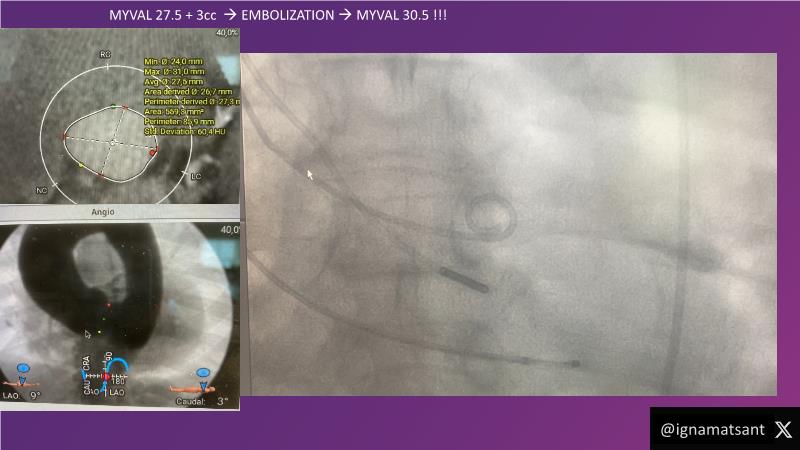

This session is a valuable resource for grasping innovative strategies in handling bifurcation and extended diffuse lesions through dedicated stenting solutions. Explore insights into the advanced Myval next-generation THV technology, unveiling its distinctive features, procedural advantages, and clinical outcomes across a diverse patient pool. Gain understanding into the CorAlign technique, ensuring accurate commissural and coronary alignment while maintaining coronary access. Additionally, delve into the techniques for precise sizing, positioning, and deploying of Myval THV.

- To understand the technique of precise sizing, positioning and deployment of Myval THV